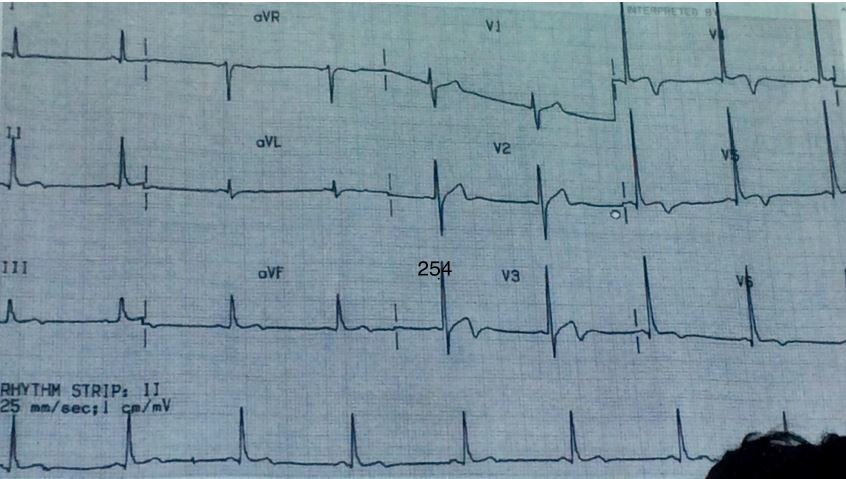

Severe Hypokalemia:

Long QT, U waves and Flat T waves with Inconstat Baseine